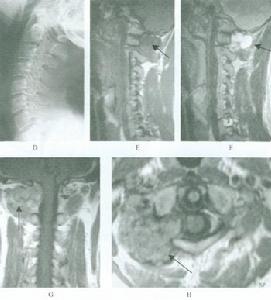

3)影像學表現

1.CT表現:

①NF1型:頭大,顳角脈絡叢非腫瘤性孤立的鈣化或沿整個脈絡叢的鈣化。蝶骨大翼發育不全,合併顳葉向眼眶疝出,搏動性凸眼,可並發腦膜瘤、神經鞘瘤及膠質瘤。

②NF2型:前庭耳蝸神經瘤,一些患者不伴有耳蝸前庭神經瘤,而有硬膜膨出可使內耳道擴大。可伴有第Ⅲ-Ⅶ腦神經鞘瘤,單發或多發腦脊膜瘤,多發脊柱神經鞘瘤。

2.MR表現:

①雙側聽神經瘤,多數以一側為重;

②多對顱神經、周圍神經的神經纖維瘤;

③合併腦膜瘤或膠質瘤;

④常伴骨骼畸形,如脊柱裂、顱骨缺損。